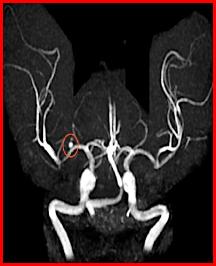

Cerebral hemorrhages are caused by the rupture of a weakened cerebral artery. Several things can undermine cerebral arteries including hypertension (classically occurring in the basal ganglia), atherosclerotic plaque, or aneurysms (such as the saccular or "berry" aneurysm visible in the angiogram to the left). Berry aneurysms usually occur near the circle of Willis. The resulting hemorrhage can occur either within the cerebral parenchyma or the subarachnoid space and can result in cerebral compression from a "mass action" effect.

Here are 3 angiograms. Each case represents either a thrombotic, hypoperfusion, and hemorrhagic stroke. Which is which?

What is a precursor lesion that can lead to cerebral hemorrhage and what might it look like?